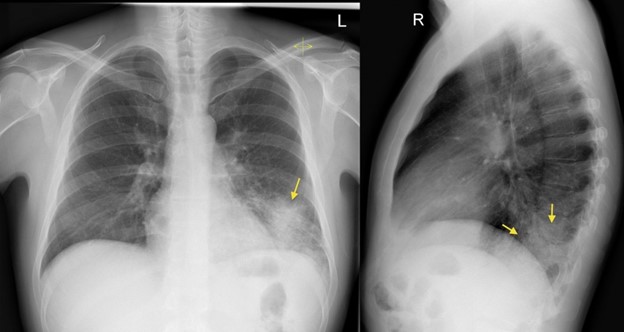

隐源性机化性肺炎(Crytogenic organizing pneumonia COP),是病因不明的肺间质炎症和纤维增生,向肺泡蔓延,导致肺泡逐渐填满蛋白质、成纤维细胞和纤维。症状是干咳、呼吸困难、发烧、全身不舒服。CT可以发现弥漫性实变、玻璃样浸润、弥漫性纤维化。与其它疾病如癌症、结缔组织病相关的,叫继发性机化性肺炎(Secondary organizing pneumonia)。究竟什么引发了这些病理改变不清楚。和其它原因不明的间质性肺炎不同,机化性肺炎肺脏的结构没有被破坏,及时治疗肺脏可能恢复正常。

第12天我接手,只管一天,代别人班。读完逐日志,发现肺科医生计划当天把甲基强的松龙降到40毫克静脉注射,每天两次。查完房,回头再把记录、化验、药物、氧气需要量读了一遍, 把CT翻来覆去看了两遍。 我认为这个病人是COP。 肺科医生上了皮质激素,是正确的措施。 但是剂量不够大,更不应该现在就减量。